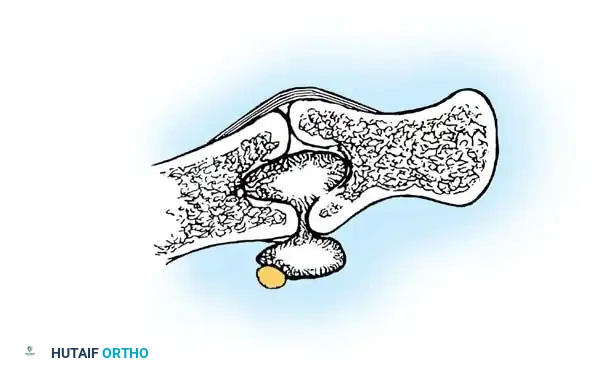

Sagittal section view revealing an intraarticular ganglion bridging the carpometacarpal joint with extensions into the substance of the capitate and fourth metacarpal.